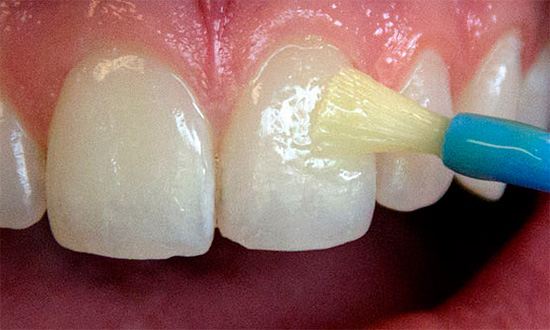

Le procedure fisioterapiche sono molto efficaci in caso di carie generalizzate: calcinazione e fluorizzazione dei denti con l'aiuto di preparazioni speciali e (o) elettroforesi.

- Mineralizzazione dei denti nella poltrona del dentista con preparazioni di calcio e fluoruro con possibili opzioni per combinare le tecniche per ottenere i migliori risultati in ciascun caso (ad esempio, il farmaco "Fluftored" per la fluorurazione profonda).